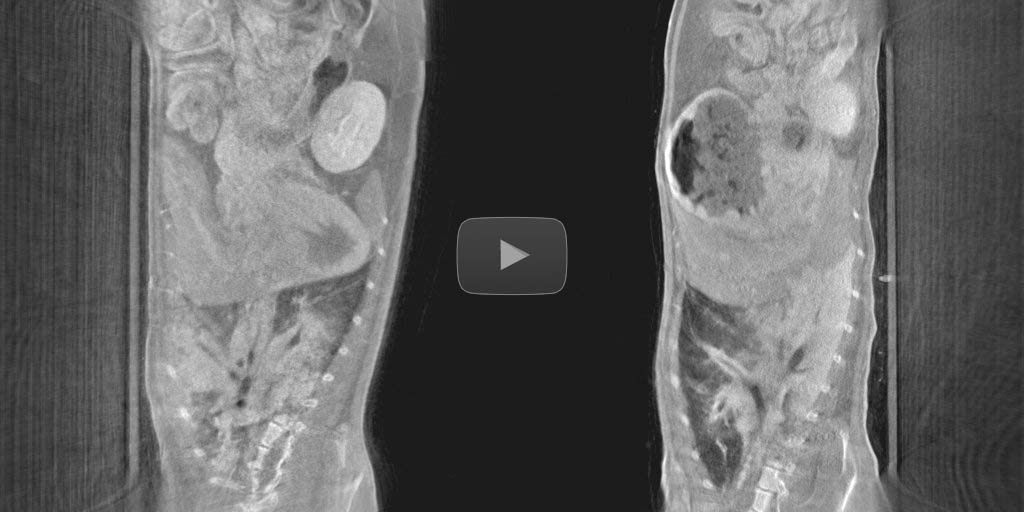

Breathing cycle detection on abdominal scans

No need of a deep anesthesia and external lung ventilation setup